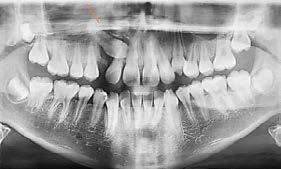

Diagnóstico radiológico

A partir de los 8 años, se puede observar radiográficamente el inicio de la reabsorción del canino deciduo (Figura 17).

El seguimiento del trayecto canino con un estudio radiográfico postero anterior, lateral de cráneo y ortopantomográfico, a partir de la edad señalada anteriormente, también es una herramienta efectiva que permite obtener un diagnóstico inicial, donde podrá observarse si se ha iniciado la reabsorción radicular del canino deciduo e identificar qué

dirección o trayecto está tomando el canino permanente (Figura 18).

Ubicación del canino

Un método sencillo para obtener el diagnóstico de inclusión canina en proceso o declarada, cuando no se realizó un seguimiento desde una edad temprana, será utilizando como herramienta de diagnóstico inicial, una ortopantomografia, donde al trazar puntos, planos y líneas de referencia en estructuras dentocraneales y en el eje longitudinal del canino propiamente, podremos ubicar tridimensionalmente el sitio de inclusión en proceso de formación radicular (estadio del 6 al 9), o definitivo, cuando el ápice se ha cerrado (estadio 10 de Nolla) y el diente no erupcionó8 (Figura 20).